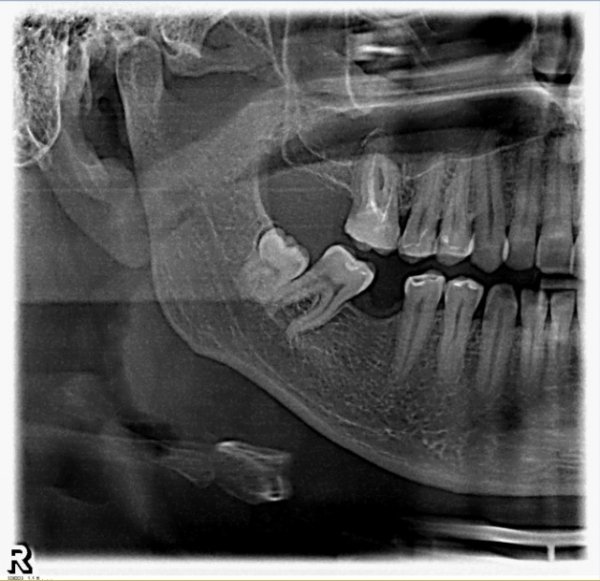

На верхней челюсти справа в районе зуба 6 образовалась небольшая припухлость, которая видна только со стороны щеки, при постукивании на сам зуб отдает болью, десна вокруг зуба не красная и не припухлая, воспаленной не выглядит, зуб залеченный.

Сделали снимок, врач, делавший снимок, направляет на удаление зуба по результатам снимка.